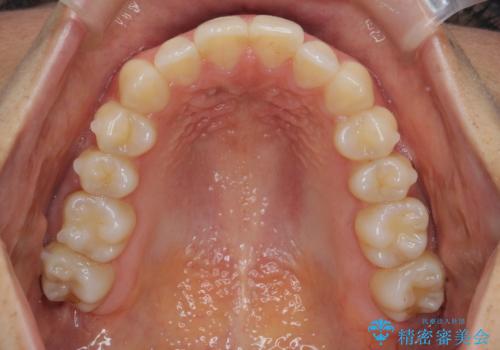

前歯のがたつきをしっかり治すマウスピース矯正

- 前歯のガタガタをきれいに並べたい、と希望され来院されました。

マウスピース矯正インビザラインのクリンチェックを用いて治療前にしっかりと歯並びのゴールのシミュレーションを行い、治療を開始します。

がたつきのないきれいな歯並びに仕上げることができ、満足いただくことができました。